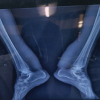

Magnetic resonance imaging (MRI) of both ankle joints was done with the below findings: (Fig. 2)

The Achilles tendons appear diffusely bulky with mild PD fat sat hyperintense intrinsic signals within, however, there is no tear noted. It appears predominantly hypointense on T2 as well as T1 imaging. Their calcaneal attachments also show no abnormality. On the right side, the maximum width of the tendon is 2.4 cm and is 6 cm cranial from the calcaneal attachment site. There is no peritendinous fluid or fat stranding seen. On the left side, maximum width of the tendon is seen to be 2.5 cm and is 7 cm cranial from the calcaneal attachment site. The visualized bones show normal marrow signal. The ankle joints appear normal without any effusion. Rest of the visualized ligaments and tendons are normal in course and signal without any evidence of tenosynovitis (Fig. 2). As the MRI findings were suggestive of xanthomatosis of the tendon Achilles, the patient was advised to evaluate their lipid profile to look for underlying hypercholesterolemia or hyperlipidemia. Serum lipid profile showed hypercholesterolemia and hyperlipidemia (Fig. 3).